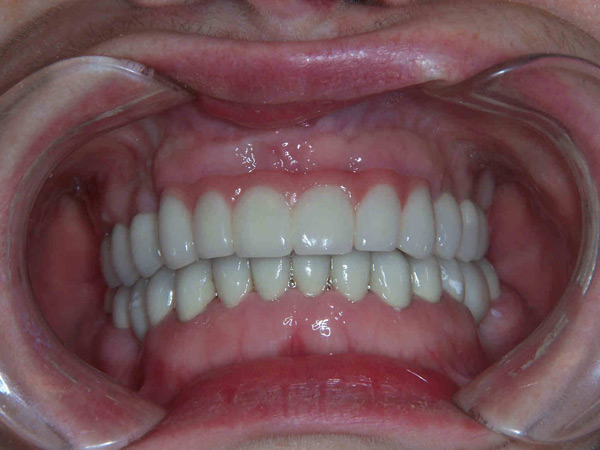

Case Study 11

Problem: This patient comes in with badly broken-down teeth and periodontal disease. Her midline is off center. She wants something that will be anchored in so she can eat well and look fabulous.

Plan: Our plan… we removed the remaining teeth and placed four implants on the lower for a fixed/hybrid prosthesis. The upper required bone grafting and then placed eight implants that will support a connector bar prosthesis.

She is happy. We’re happy. Mission accomplished!